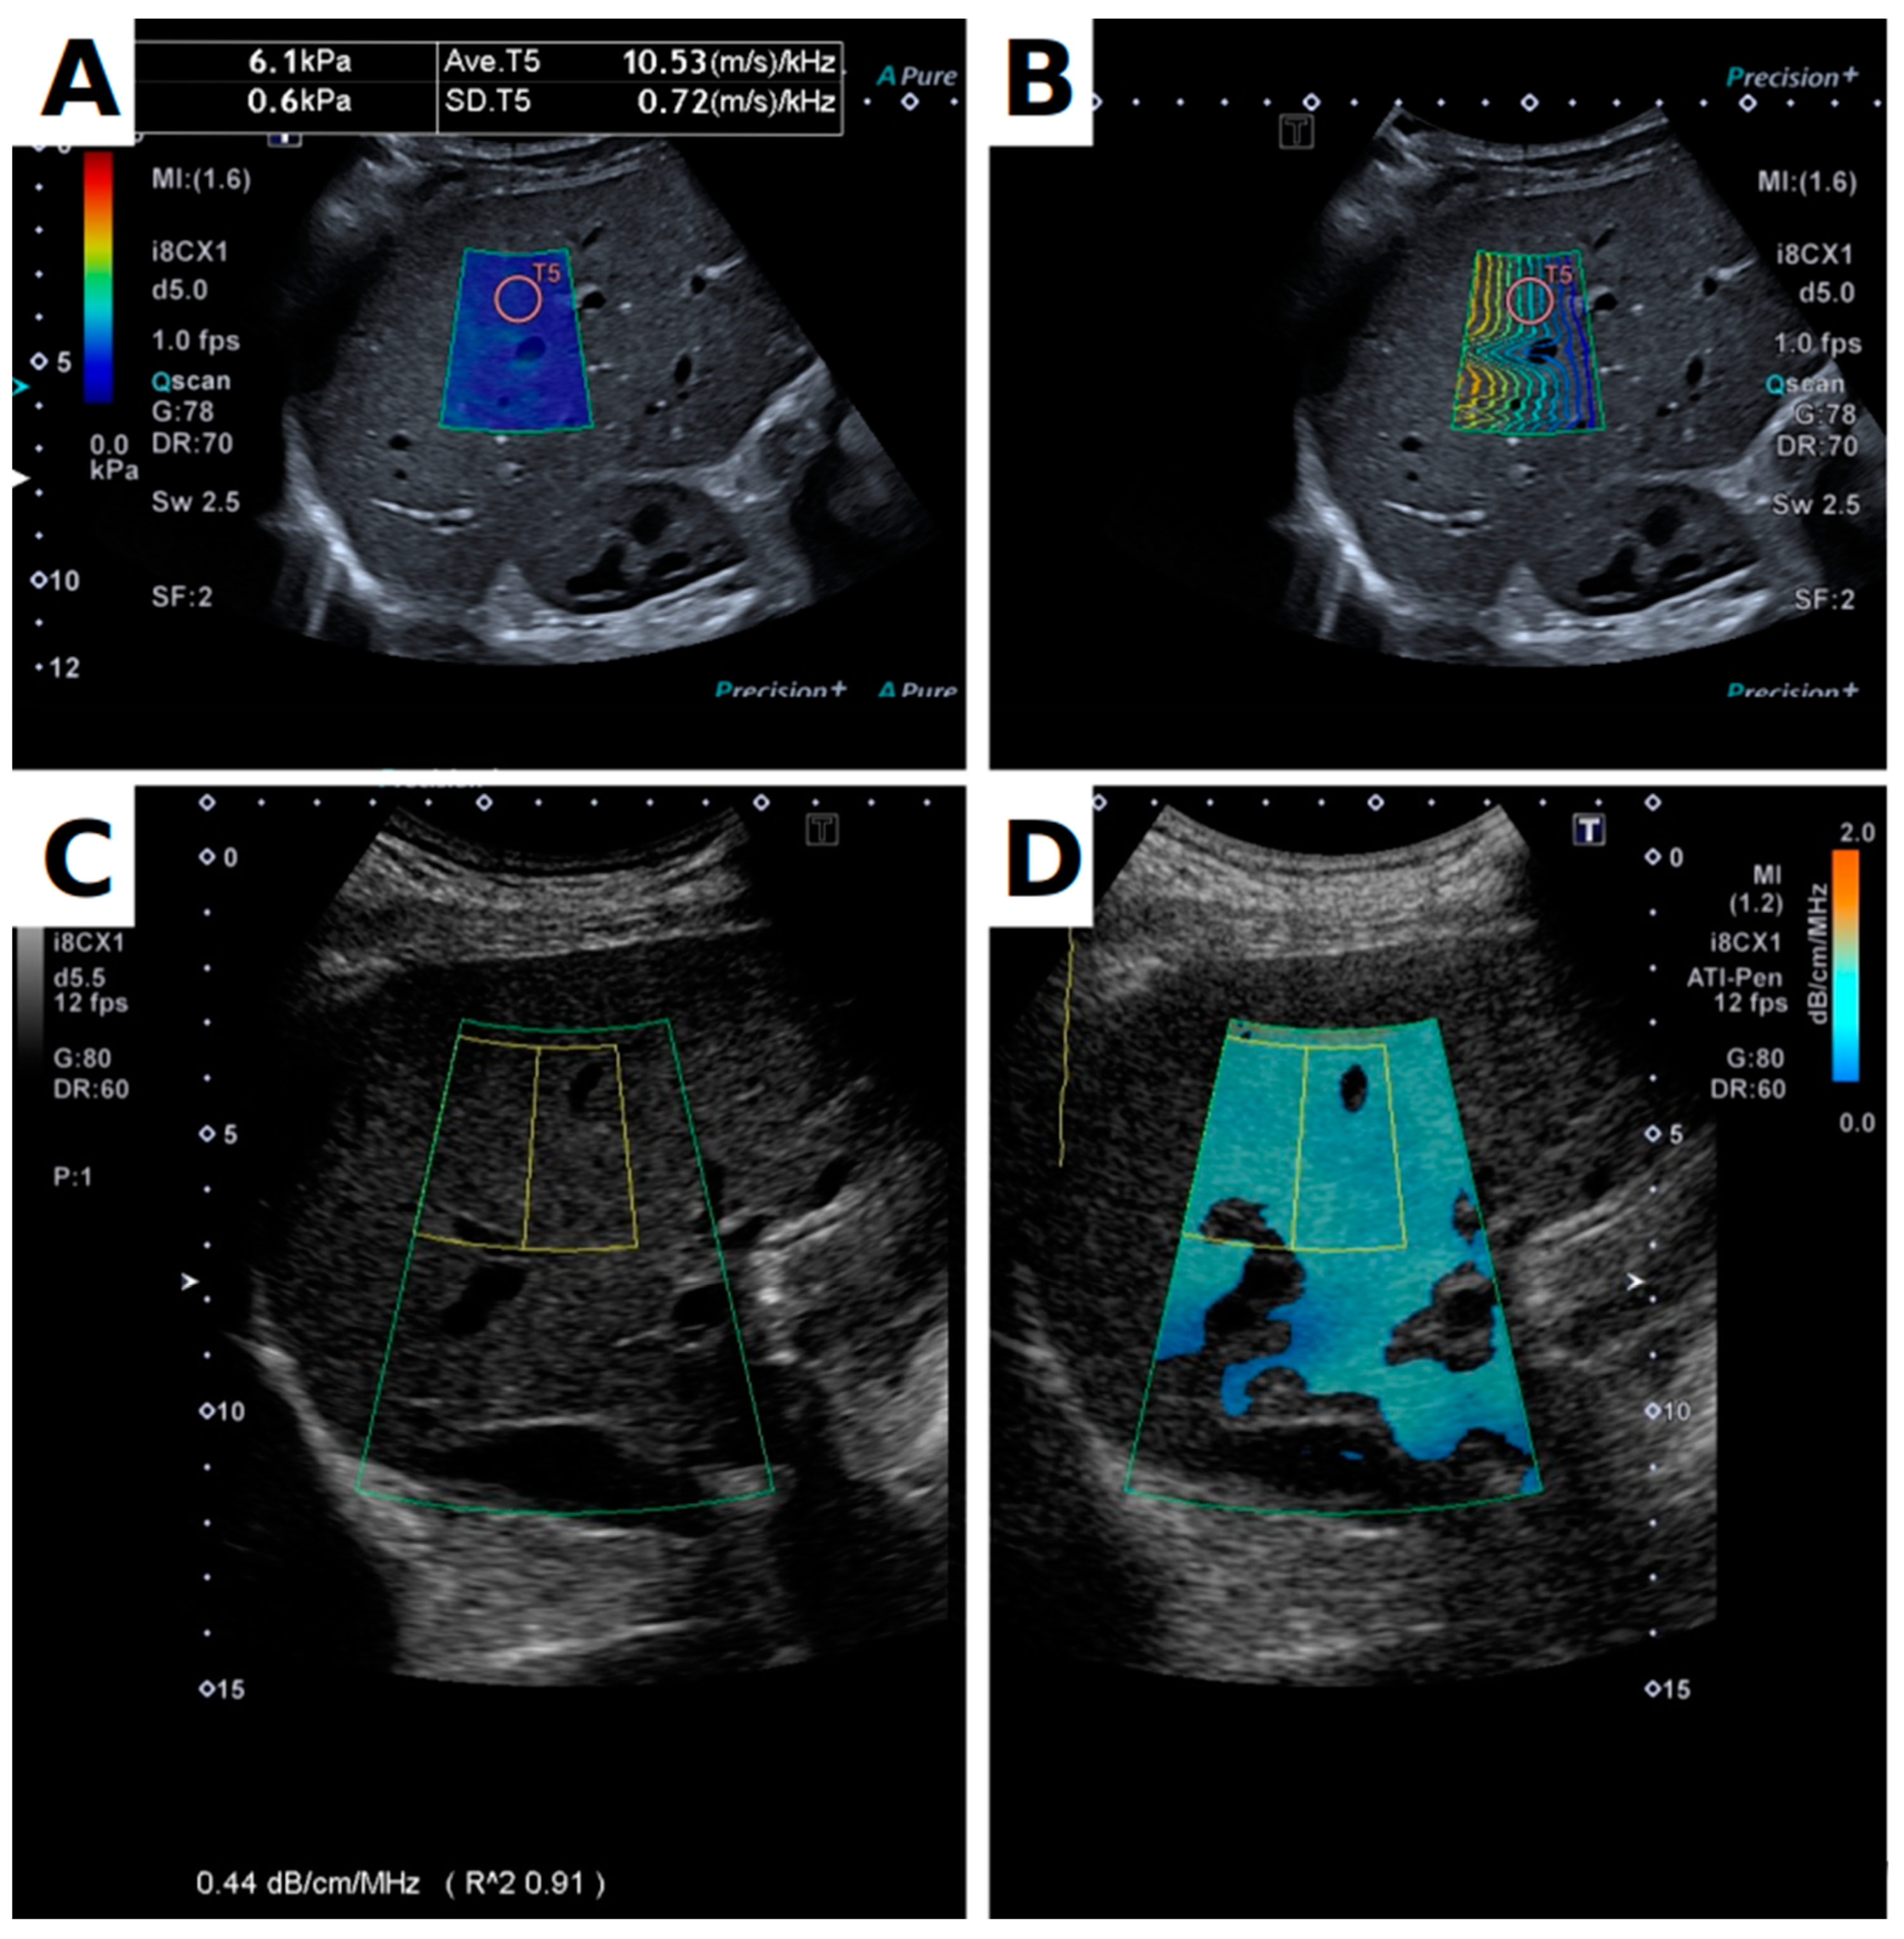

2.2. Equipment and Protocol